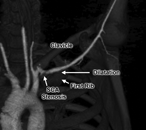

Effort thrombosis of the subclavian artery as a consequence of a unique anomaly

Evan R Brownie and Robert W Thompson

Journal of Surgical Case Reports, Volume 2018, Issue 4, April 2018, rjy072, https://doi.org/10.1093/jscr/rjy072